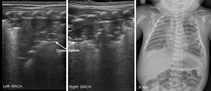

新生儿正常肺组织在超声下呈低回声,胸膜线与A-线均清晰显示,呈光滑、清晰、规则的高回声,二者与等间距平行排列;实时超声下肺滑清晰存在,无或可有少数几条B线;但无胸腔积液、肺实变(图1)。

本组MAS患儿的肺脏超声主要表现(表1):(1)肺实变伴支气管充气征:见于所有患儿,重度患儿通常为范围较大、且边界不规则(锯齿状边缘)的实变区(图2,图3,图4);而轻度患儿则以小范围的局限性实变为主要表现(图5);但双侧肺脏实变范围的大小可以不同,而且同一侧肺脏野可以存在大小不同的实变区(图4,图5,图6)。(2)胸膜线异常与A-线消失,见于所有患儿,胸膜线异常表现为病变区胸膜线消失或增粗模糊(图2,图3,图4,图5,图6)。(3)肺不张,是严重肺实变的表现,见于重度患儿,本组12例(17.9%)(图7),严重大面积肺不张时可在实时超声下见到肺搏动和动态支气管充气征。(4)胸腔积液,见于9例(13.4%)患儿(图7)。(5)B-线或AIS,在实变区以外肺野则以AIS或B-线为主要表现。